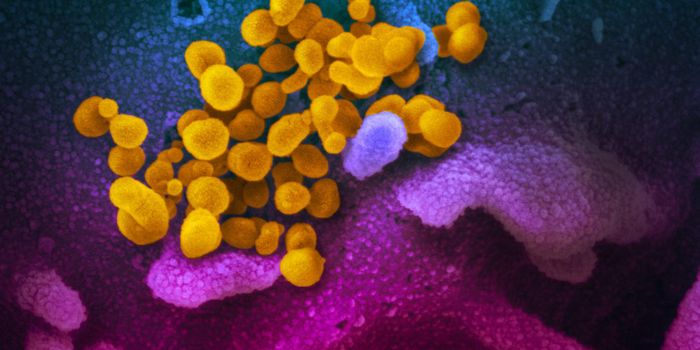

JUL 05, 2020Cell & Molecular BiologyThe pandemic virus SARS-CoV-2 enters the body through the respiratory system to cause the illness COVID-19. But we know ...

MAR 18, 2020MicrobiologySARS-CoV-2 is a coronavirus that causes an illness called COVID-19. There are now well over 210,000 confirmed cases worl ...

APR 06, 2020Genetics & GenomicsSARS-CoV-2 is the name for the pandemic coronavirus that causes the illness COVID-19, which affects people in extremely ...